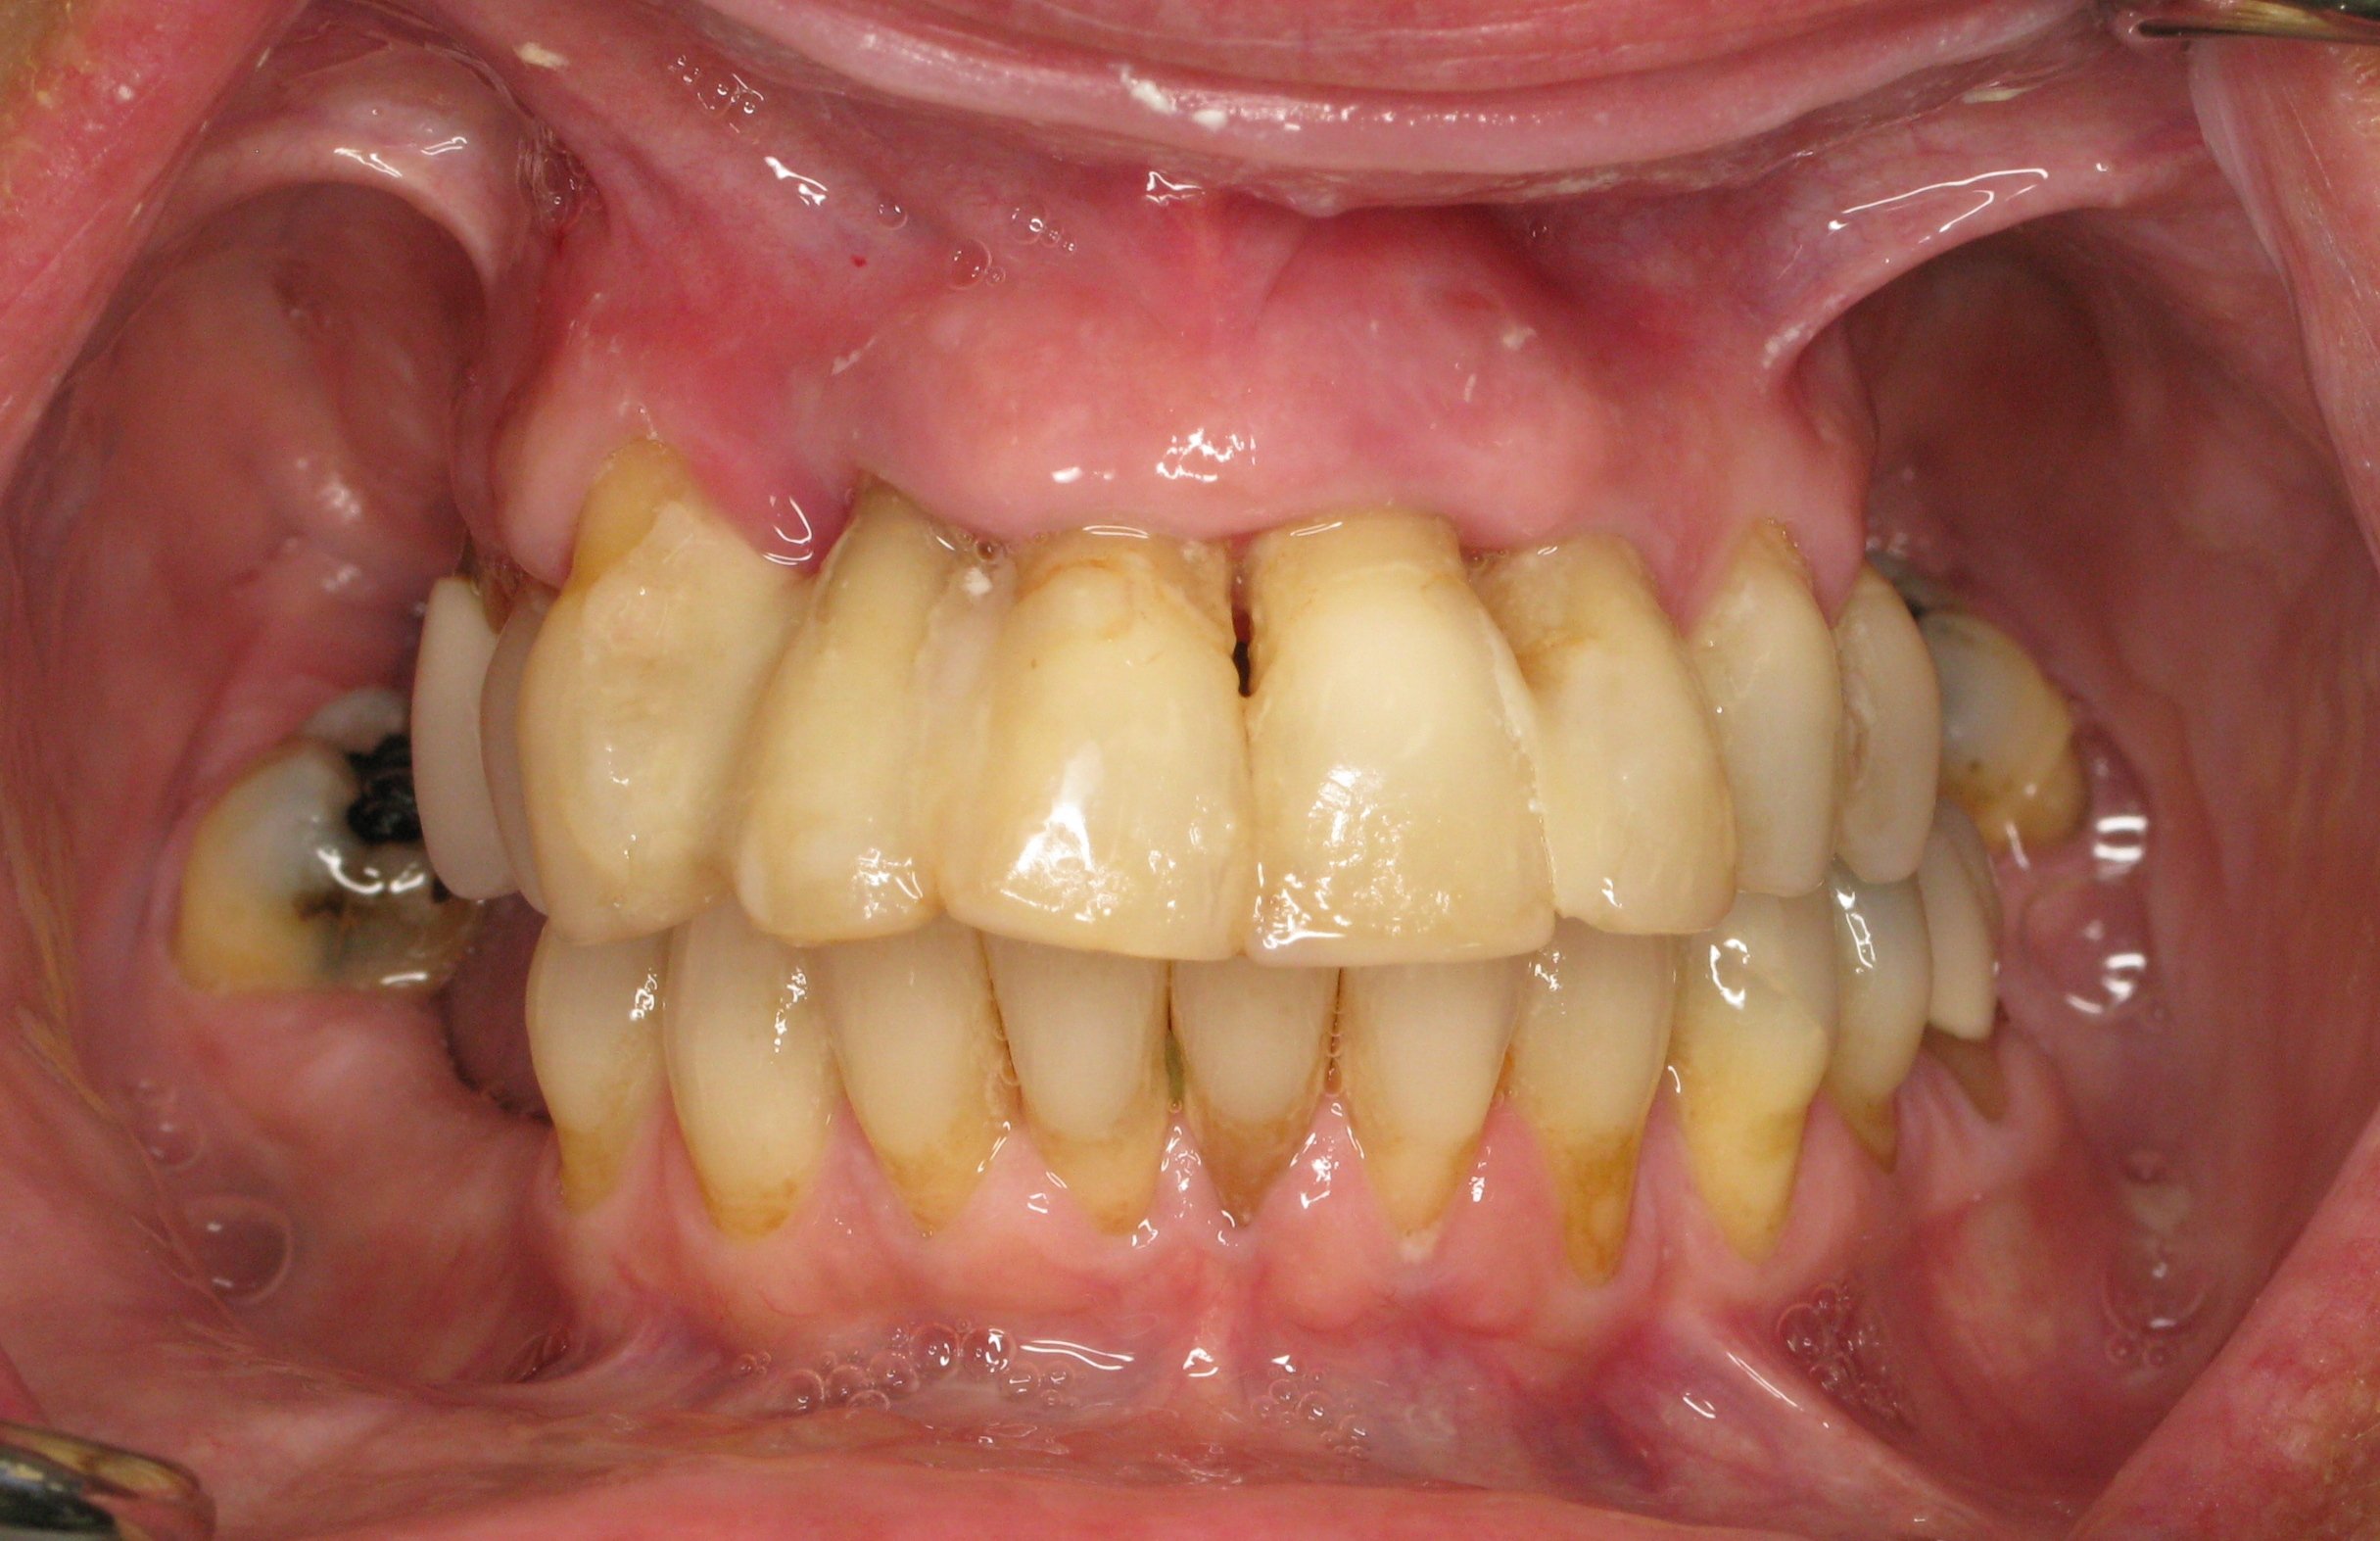

Patient came in for a second opinion as she was told from all the other dentists that her only option was a removable denture. She had neglected the dentist due to dental fear which resulted in bone loss and hopeless teeth. We managed to save her lower teeth and the upper was fixed with smile in a day in which the teeth were extracted and implants were placed with a fixed denture inserted all within a few hours. She was able to fully restore here smile despite having bone loss.